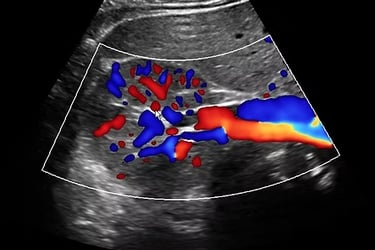

Abdominal Aortic Aneurysm

The aorta and its branches take the blood from the heart down to the abdomen and legs. We can assess for dilatation of the arteries called an aneurysm which often have no symptoms and plaque build up causing narrowing of the artery.

Renal Doppler

A renal Doppler ultrasound is performed to assess the blood flow in the renal arteries, which supply blood to the kidneys. It helps identify any blockages or narrowing of these arteries, which can lead to conditions like renal artery stenosis or high blood pressure.